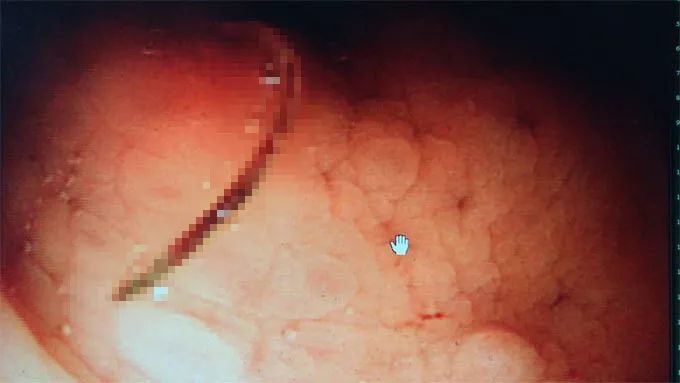

第二天肠镜检查,显示器屏幕里清晰地显示出一条虫子在刘女士的肠子里游动,长约1厘米,C型,还不停摆弄着尾部,头好像要往肠子里钻,把肠粘膜都钻出了一个破口,不断有血液流出来。

肠镜下的钩虫

原来,导致刘女士出现一系列症状的,正是这种寄生虫。最后,检验科医生在显微镜下证实,这是美洲钩虫!